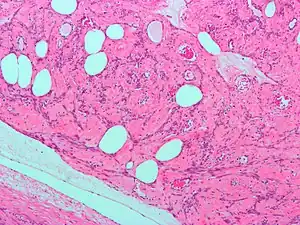

Histopathology of uterine fibroids typically show smooth muscle in a whorled (fascicular) pattern.[32] -

Microscopically, tumor cells resemble normal cells (elongated, spindle-shaped, with a cigar-shaped nucleus) and form bundles with different directions (whorled). These cells are uniform in size and shape, with scarce mitoses. There are three benign variants: bizarre (atypical); cellular; and mitotically active.